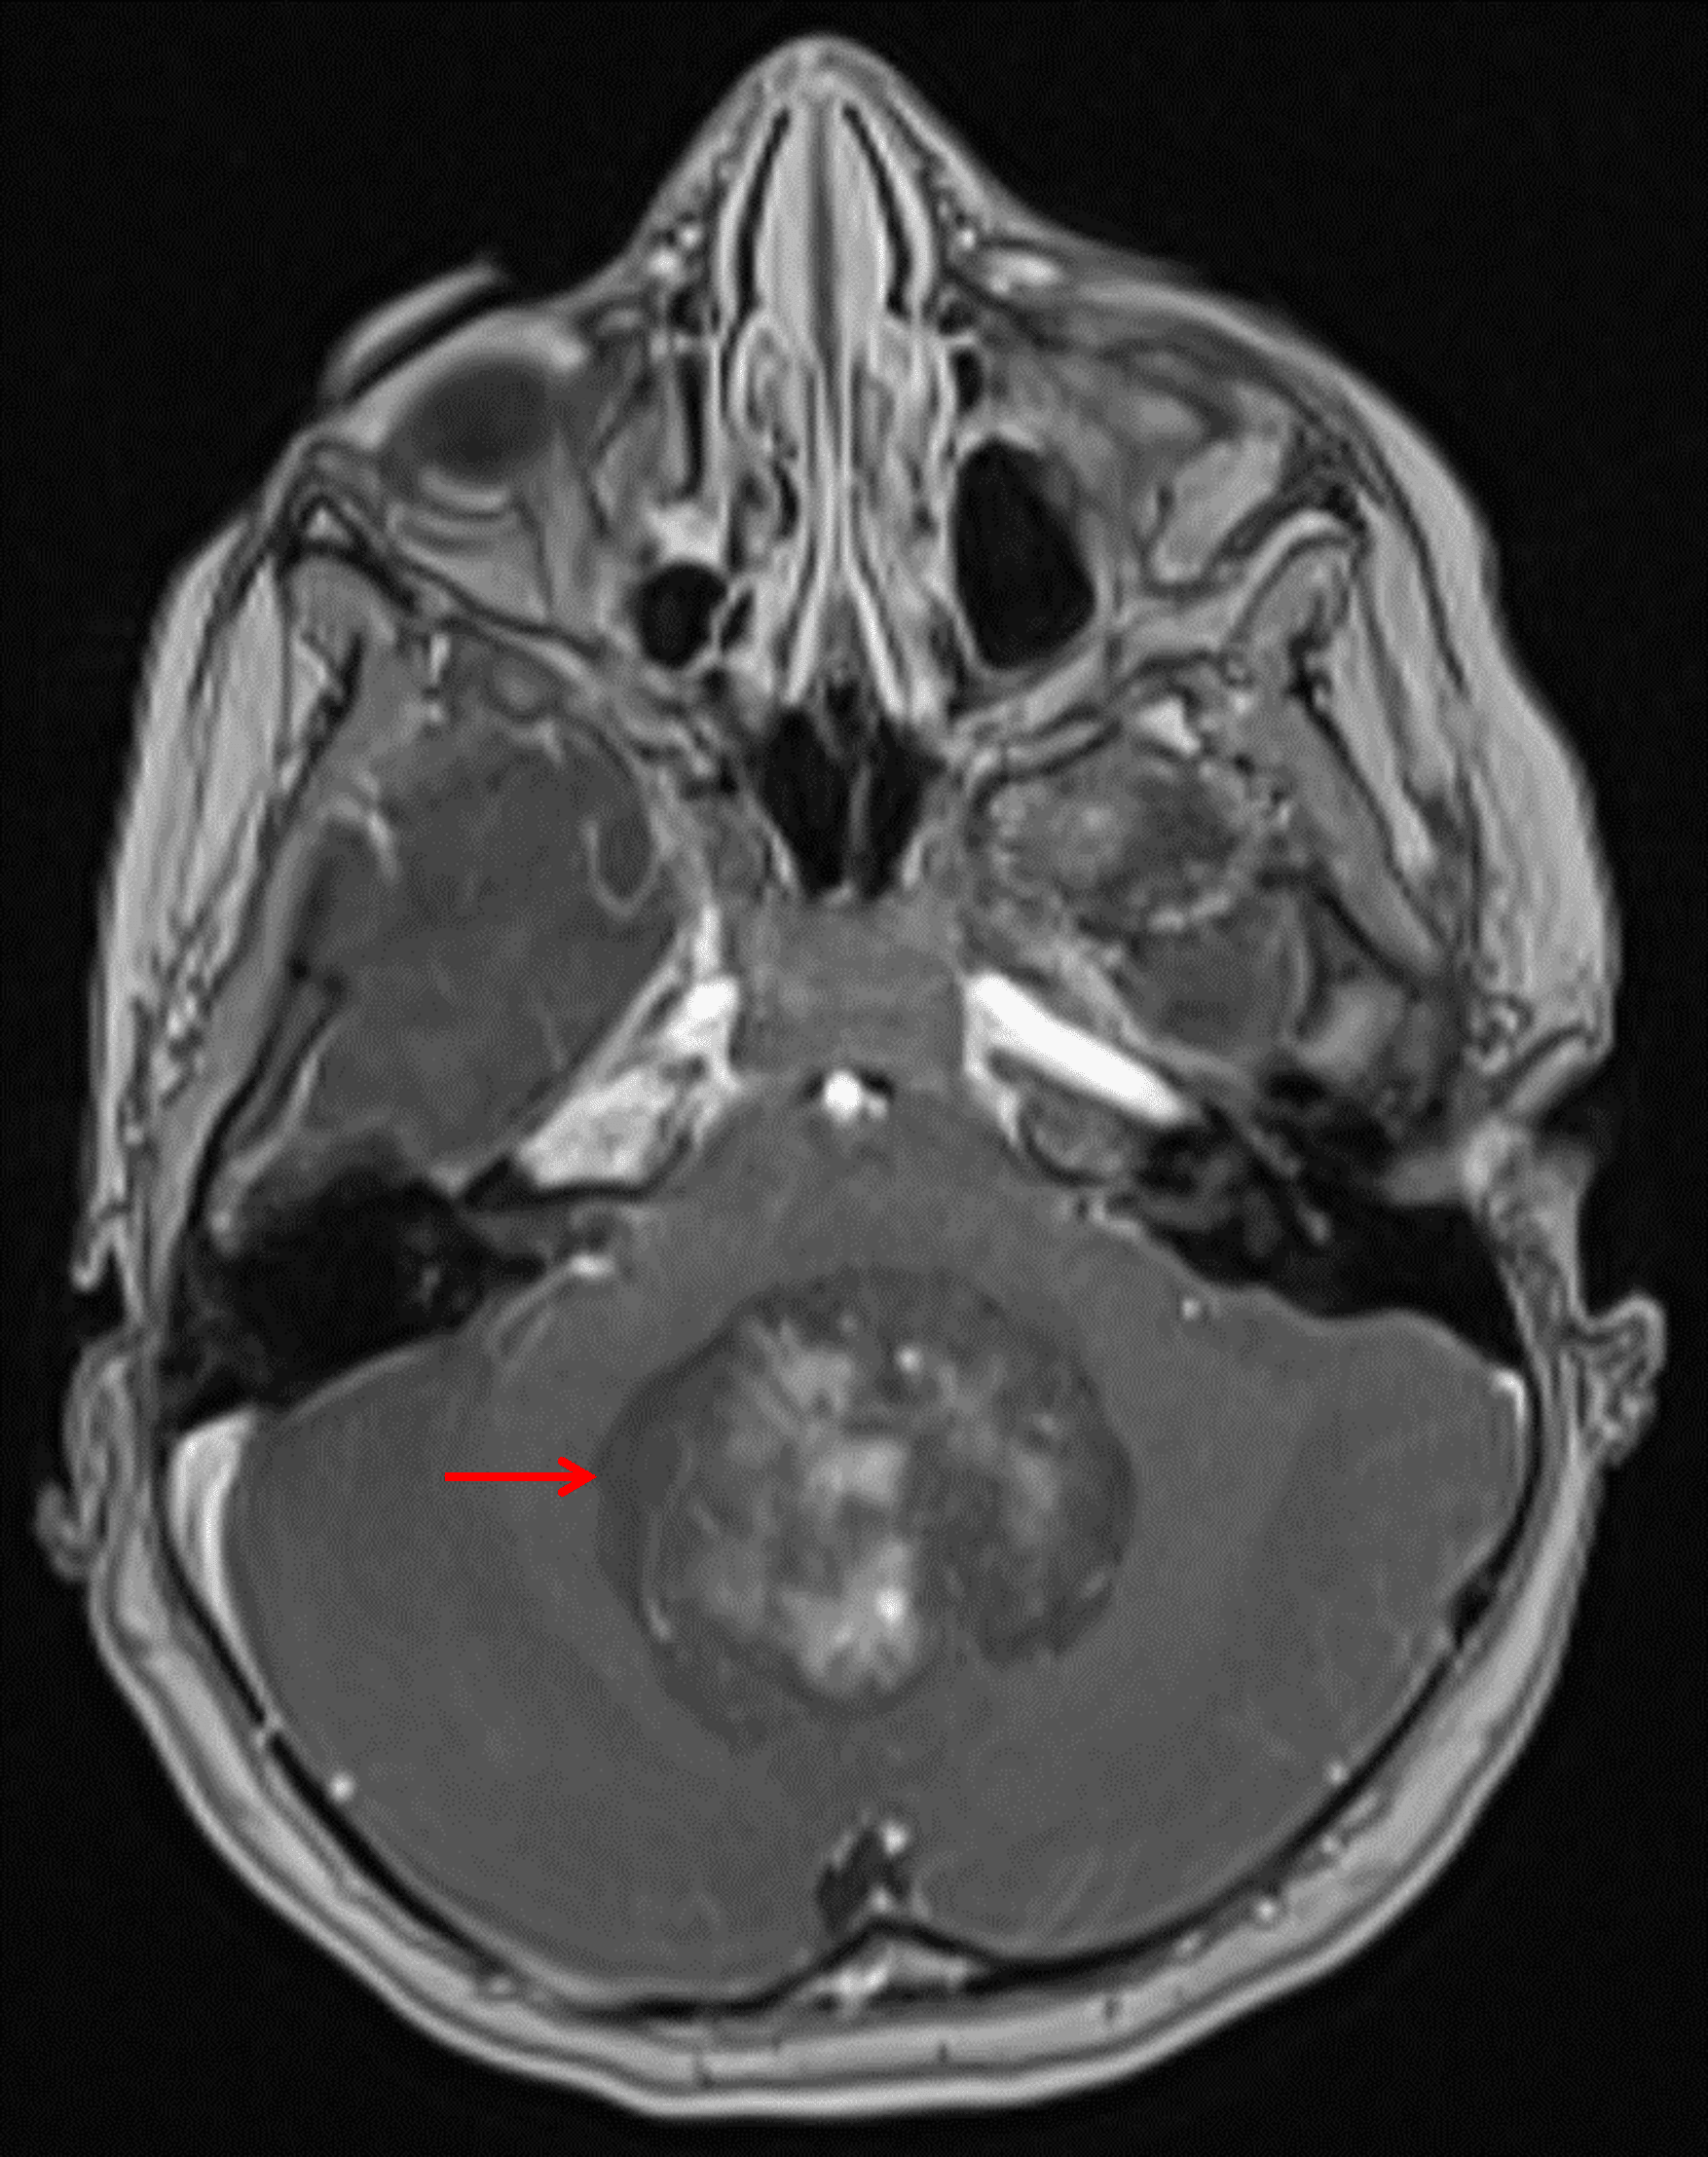

Heterogeneously enhancing mass centered in the vermis and fourth ventricle (red arrow).

• Heterogeneously enhancing mass centered in the fourth ventricle measuring 5 x 4 x 3 cm with associated diffuse restricted diffusion

• Resultant effacement of the fourth ventricle and obstructive hydrocephalus with subependymal edema involving the lateral and third ventricles

• Inferior displacement of the cerebellar tonsils into the foramen magnum with crowding of the upper cervical spinal cord